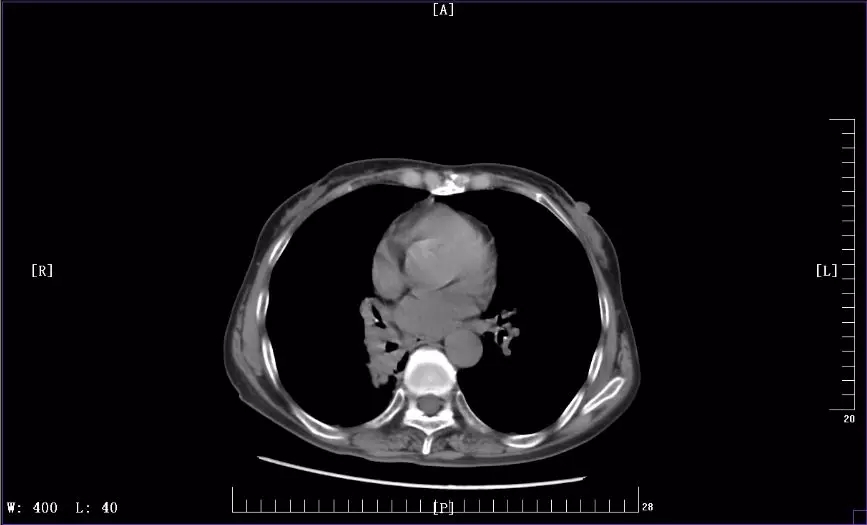

下图是徐丽参加KEYNOTE-407临床试验前后CT影像对比图:

2018年12月最近一次治疗后CT影像